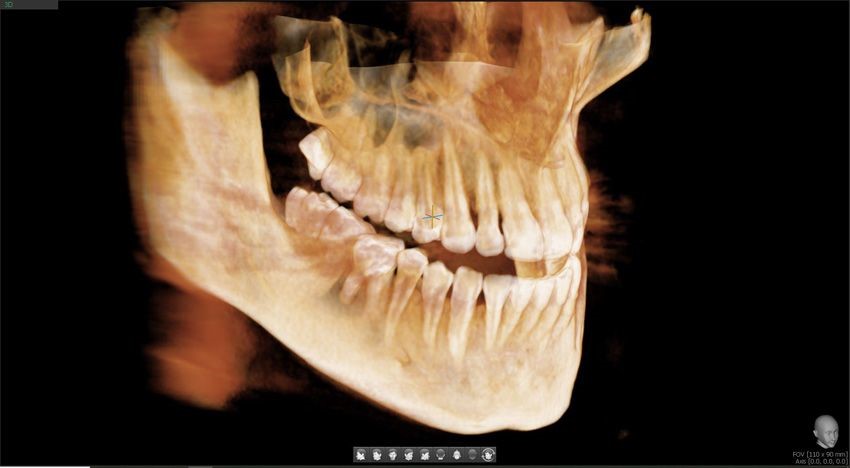

W przeciwieństwie do pantomogramu pokazuje struktury w trzech wymiarach. Oznacza to, że widzimy dokładną szerokość i wysokość kości, przebieg korzeni oraz ułożenie zębów do nerwów czy zatok.

Kiedy potrzebne jest 3D (CBCT)?

Tomografię 3D zalecamy najczęściej:

- przed wszczepieniem implantu,

- przy skomplikowanym leczeniu kanałowym (endo),

- gdy ząb ma nietypową budowę,

- przy planowaniu leczenia w sąsiedztwie nerwów,

- w bardziej złożonych przypadkach ortodontycznych

Badania naukowe pokazują, że w implantologii i trudnych przypadkach endodontycznych obraz 3D znacząco zwiększa bezpieczeństwo i przewidywalność leczenia.

Dzięki temu możemy zaplanować zabieg z najwyższą precyzją i ograniczyć ryzyko niespodzianek.